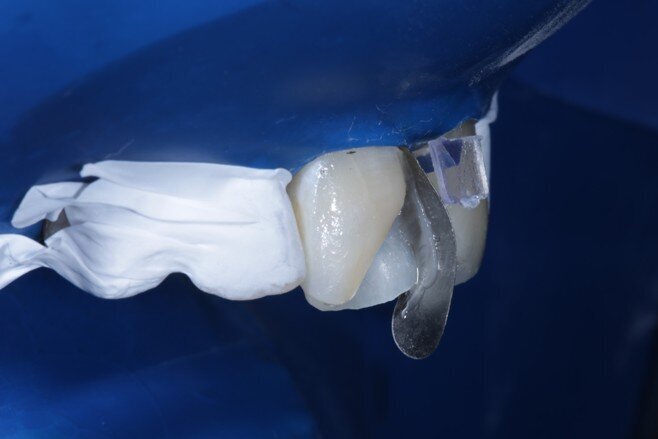

Two weeks later, the shade [ Fig 3 ] stabilized and the teeth were ready for bonding. We observed that the central incisors were still darker than the neighboring teeth. Direct composite veneers were planned with the help of a lab made wax up [ Fig 4 ] and a putty index. Bevels were placed and most of the preparation was in enamel. After the total etch protocol, 5th generation bonding agent was used. 3M Z350XT shades were used for the build up. A2 Enamel shade was used for the palatal shell [ Fig 6 ] and the proximal walls [ Fig 11 ].

Fig 9 Sectional matrix placed vertically

Fig 10 Enamel shade for proximal box layering